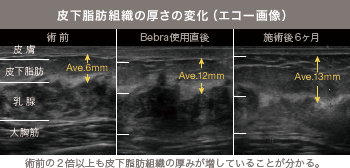

定着しやすい環境と整えて大きく乳房拡張器「Bebra」

脂肪は圧迫に弱く、定着には十分なスペースが必要です。特に痩せ型の方やバストがもともと小さい方は、皮膚が伸びにくく、

バストの中が満員電車のようにぎゅうぎゅうになってしまいやすいです。

ナチュラルバスト豊胸では乳房拡張器「Bebra」の併用も可能。あらかじめ

皮膚や組織を柔らかく広げ、ゆとりのある環境を用意することで、一般的に難しいケースでも、自然なバストアップが望めます。

術前・術後の無料エコー検査

- 組織の厚みを測定し、適応を診断

- 最適な注入プラン設計

- 術後の状態を見える化